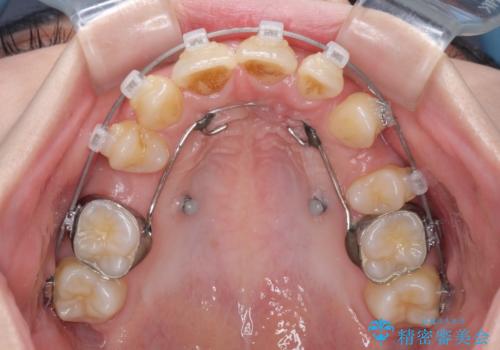

出っ歯を治したい ワイヤー装置による抜歯矯正

- クリアブラケット

- 1年10ヶ月

口元を積極的に引っ込めるために、上下左右の小臼歯を4本抜歯することとしました。

右上前から2番目の歯が欠損しているため、①矯正治療により欠損部にスペースを作りインプラント補綴を行って前歯を左右対称に揃える、②左右非対称となるが、欠損補綴を行わずに排列する、のいずれかとなりますが、患者様と相談の上②にて矯正治療を行うこととしました。

変則的な歯列であったため、奥歯がしっかりと咬み合うのか、前歯はしっかりと排列できるのかと不安ではありましたが、結果としてはきれいに整った歯列にて終了することができました。